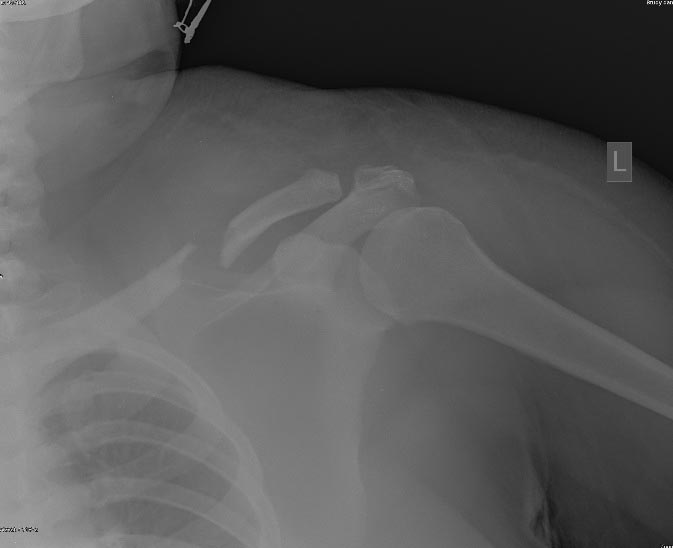

А разрыв (вывих) АКС есть? ...Прямую бы проекцию посмотреть!

Снимок до... и после.